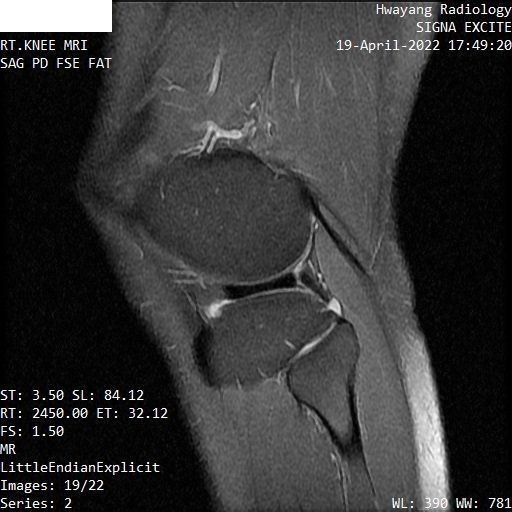

무릎연골 파열 mri좀 봐주세요 파열이 맞는지 궁금합니다.

오른쪽 무릎이 아파서 mri 찍어봤는데 집근처 병원에서 연골파열이라고 하는데

무릎주사만 맞으면서 치료하면 괜찮은 정도인지 좀 봐주시면 감사하겠습니다.

MRI 컷을 위와 같이 배열해놓은 것으로는 명확한 감별이 어렵습니다.

다만 연골부위의 MRI 상 이상 소견이 있는 것은 사실입니다.